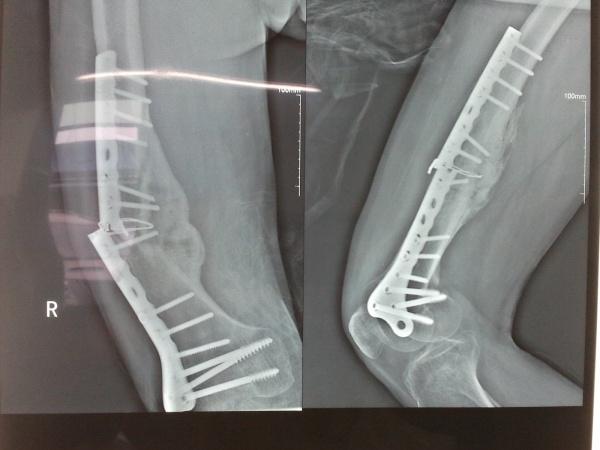

跟骨骨折重建钢板内固定